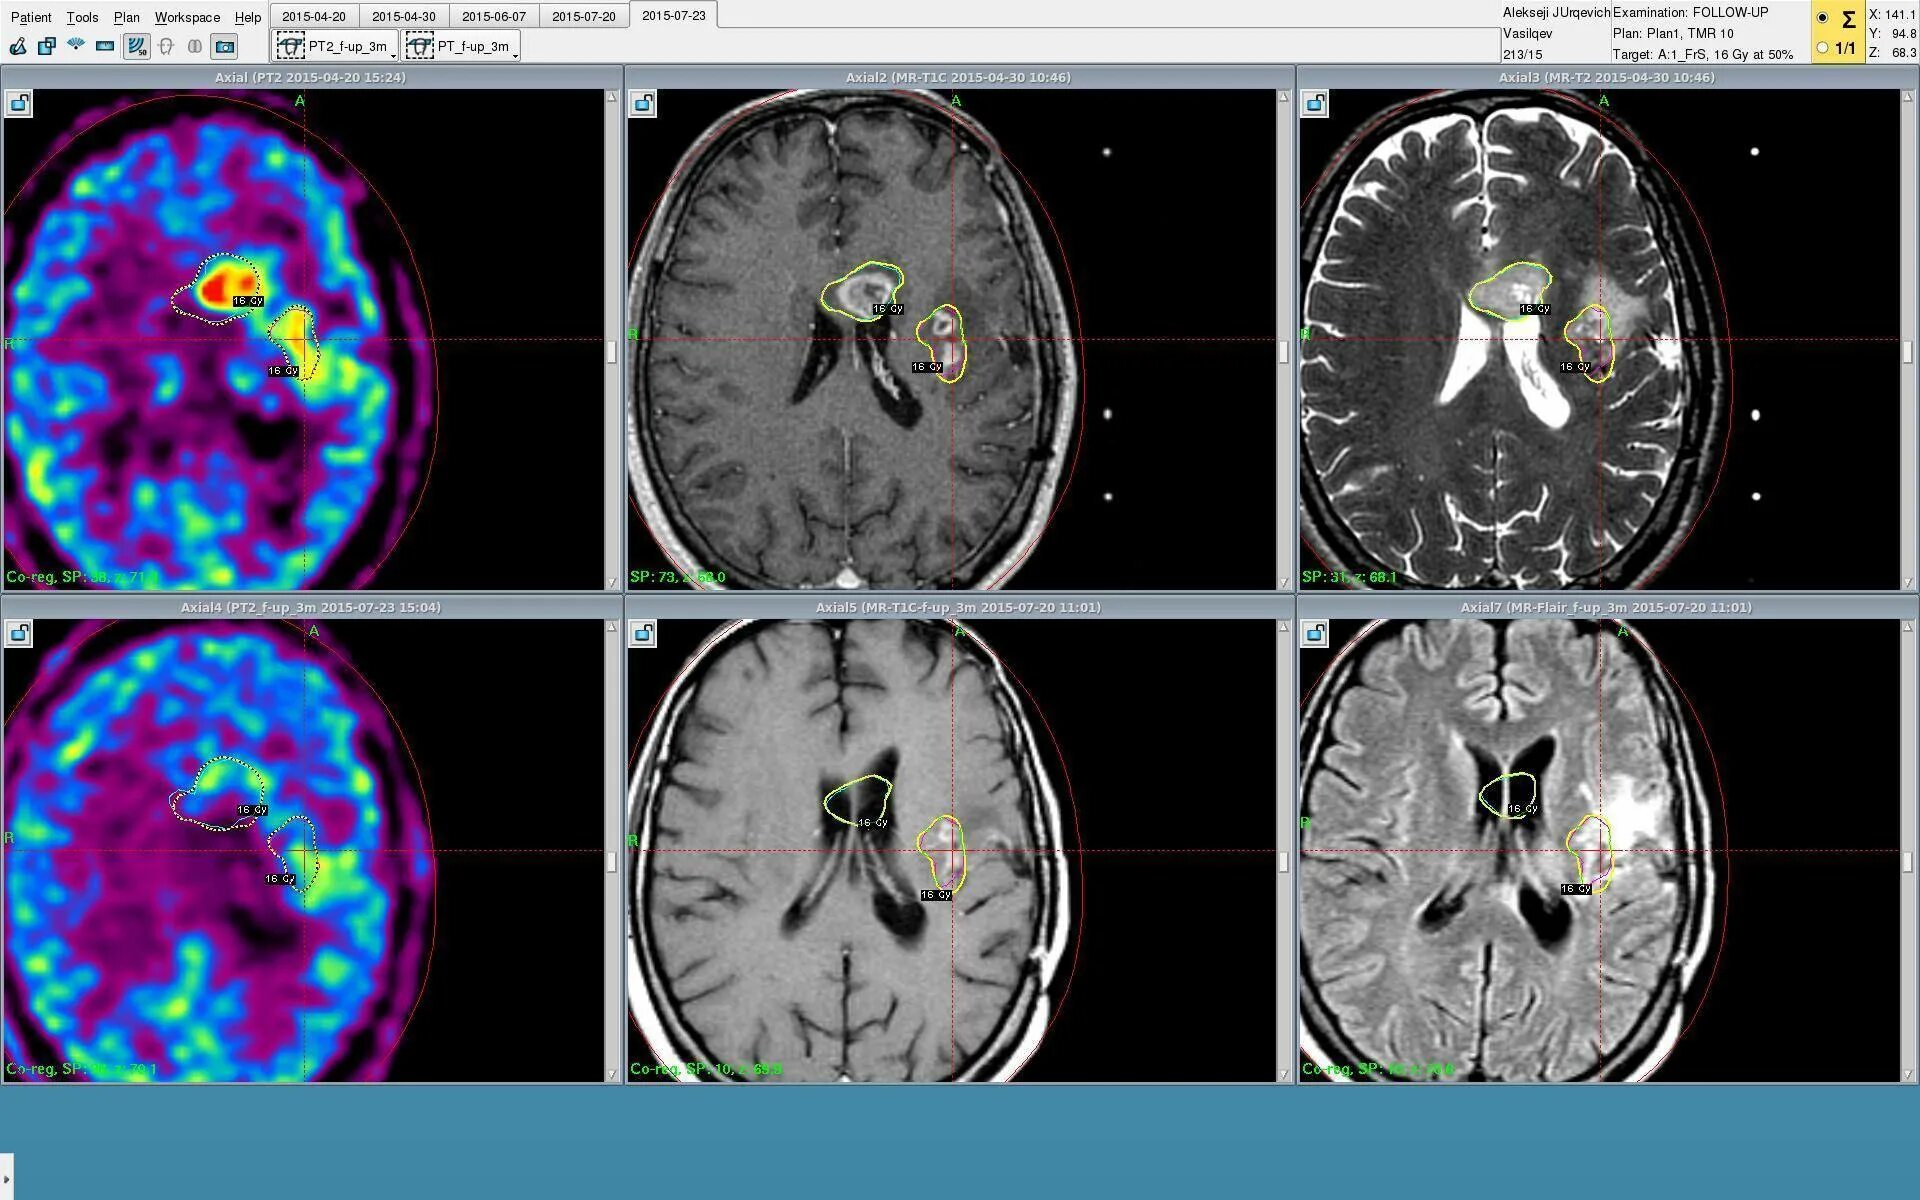

Терапия при опухоли мозга